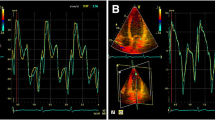

Measurements of PMs obtained from 3DE are presented in Table 3. The total ALPM and total PPM CSA were significantly larger in patients with HC than in controls (1.92 ± 0.81 vs. 1.15 ± 0.47 cm2; p = 0.001 and 1.46 ± 0.62 vs. 1.08 ± 0.37 cm2; p = 0.031, respectively). Figure 1 demonstrates an example of the 3DE analysis of the PM area. There was no significant difference in the number of ALPMs and PPMs between patients with HC and controls. Moreover, bifid and accessory PMs were not observed more frequently in patients with HC than in controls. Figure 2 shows an example of a patient with HC and a bifid PM, and Fig. 3 demonstrates an example of an accessory PM visualized by 3DE.